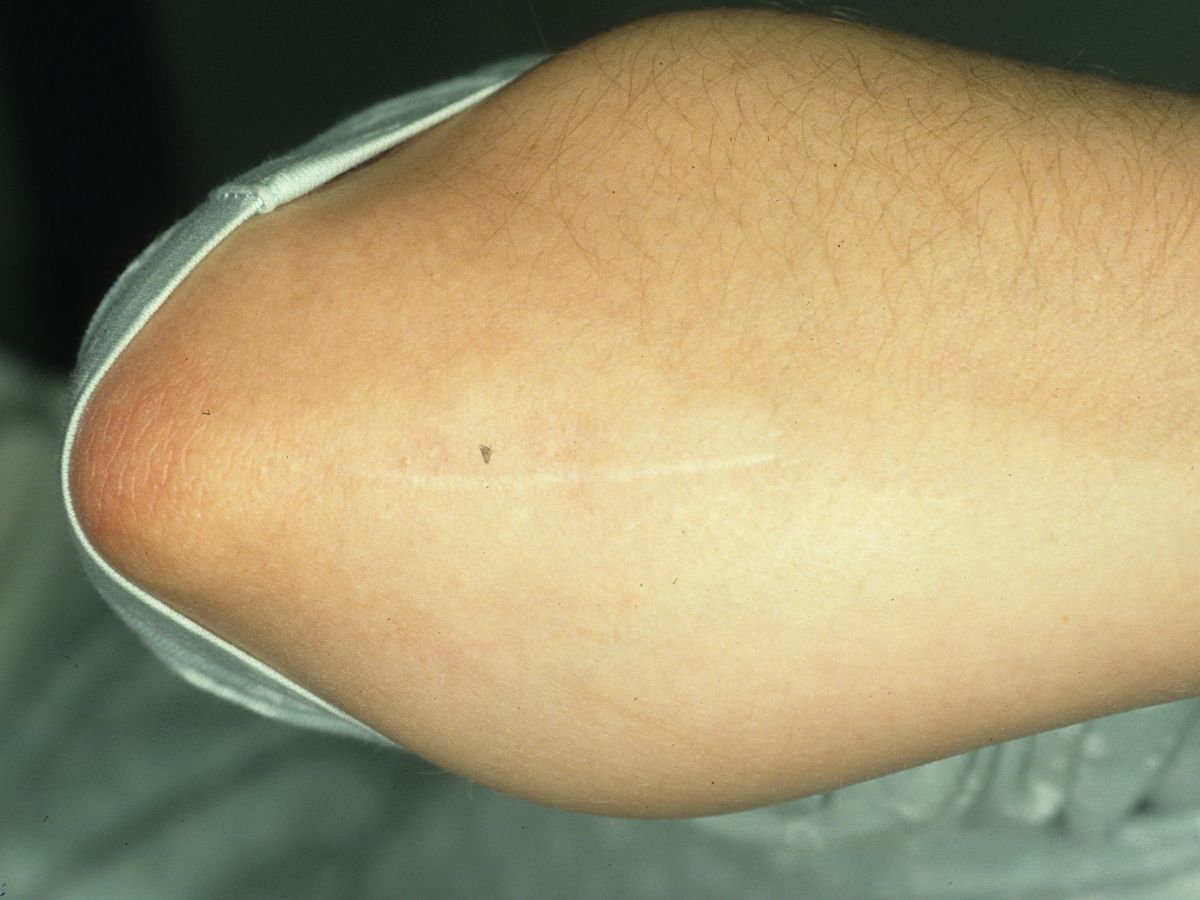

| Donor site. |